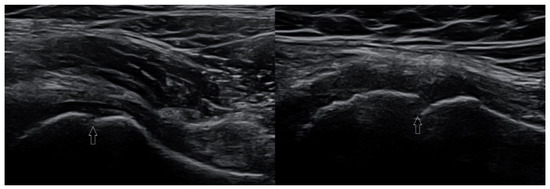

3.2.3. Ligament Injuries

- Szczepaniak, J.; Ciszkowska-Łysoń, B.; Śmigielski, R.; Zdanowicz, U. Value of ultrasonography in assessment of recent injury of anterior talofibular ligament in children. J. Ultrason. 2015, 15, 259–266. [Google Scholar] [CrossRef]